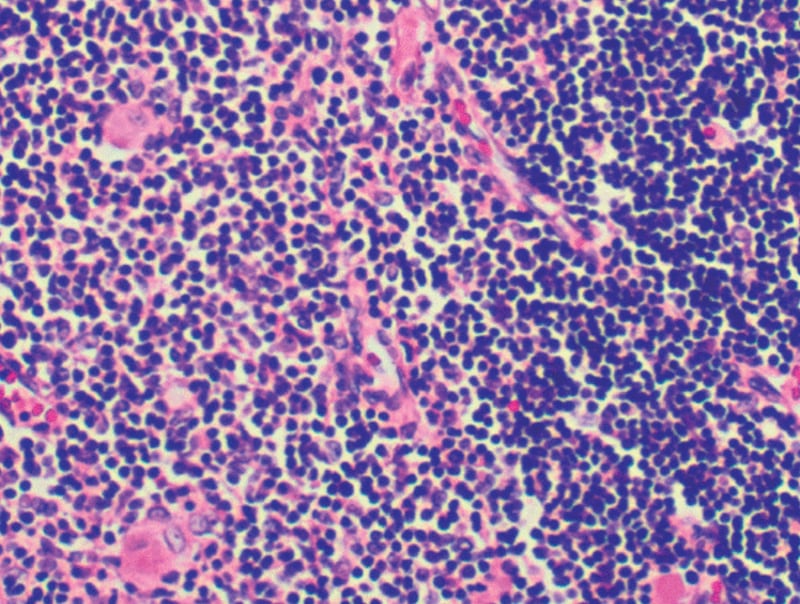

El trabajo de los galardonados se centró en identificar a los guardianes de seguridad del sistema inmunitario: las células T reguladoras (o Tregs). Estas células son un tipo de linfocito T que actúan como “moderadoras”, frenando la acción de otras células inmunes potencialmente dañinas cuando intentan atacar tejidos propios, lo que mantiene el equilibrio y la homeostasis inmunológica.

Shimon Sakaguchi fue pionero en 1995 al identificar una nueva clase de células T, desafiando la creencia predominante de que la tolerancia inmunológica se establecía únicamente en el timo. Su descubrimiento sentó las bases para el concepto de tolerancia periférica.

Mary E. Brunkow y Fred Ramsdell realizaron un descubrimiento clave en 2001 al identificar el gen FOXP3, esencial para el desarrollo y la función de las células T reguladoras. Su trabajo explicó por qué ciertas mutaciones genéticas pueden hacer que el organismo sea vulnerable a enfermedades autoinmunes.